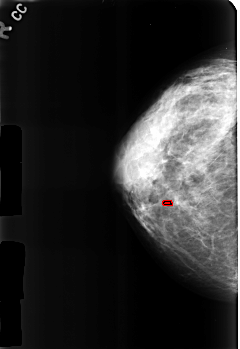

B_3184_1.LEFT_CC

LEFT_CC LINES 4608 PIXELS_PER_LINE 3184 BITS_PER_PIXEL 12 RESOLUTION 50 NON_OVERLAY

FILE: B_3184_1.RIGHT_CC.OVERLAY

TOTAL_ABNORMALITIES 1

ABNORMALITY 1

LESION_TYPE CALCIFICATION TYPE LUCENT_CENTER DISTRIBUTION N/A

ASSESSMENT 2

SUBTLETY 3

PATHOLOGY BENIGN_WITHOUT_CALLBACK

TOTAL_OUTLINES 1

BOUNDARY